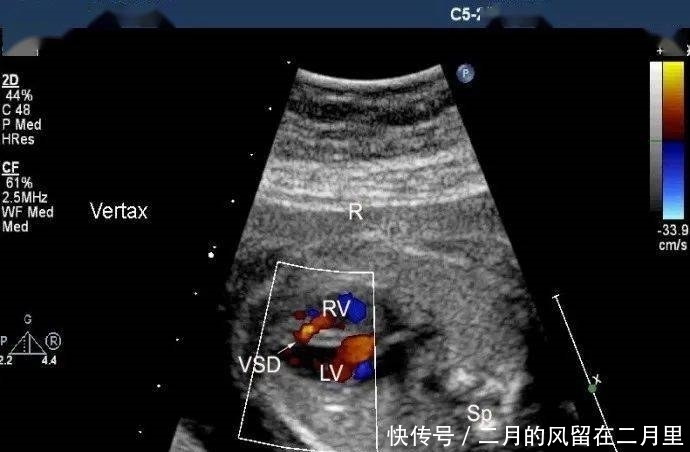

以下是我们掌中宝里几张图,很典型,很清晰。

VSD的超声声像图特征:

(1)室间隔连续性中断,缺损部位断端“回声增强”;

(2)缺损处出现双向分流,CDFI检测可见不同时相红蓝双向的血流